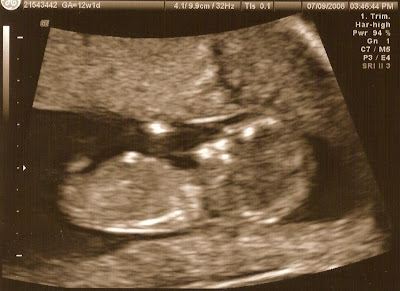

Next, she wanted to do the ultrasound. She said, "let's try the abdominal approach first." (To me this implied that we would eventually do both the abdominal and the vaginal approach, but that was not the case.) She said that it was fine that I had an empty bladder. She placed the probe on my suprapubic area and after just a moment of searching, Blueberry popped into view. It was definitely blurrier than the pictures at the RE's office. I'm not sure if that was due to the abdominal approach or whether it was simply a poorer-quality machine. Anyway, I was thrilled to see Blueberry again at any angle, and he/she gave a few waves and kicks to say hello. I could see the flicker of the heartbeat, but the NP said, "we don't measure that anymore because it doesn't matter what the heartrate is in the first trimester." I don't really buy that explanation, but I'll just assume that it was still OK. She did give me a bunch of printouts, but most are very blobby-looking. The best one is this:

I think you'll agree that the 9w0d ultrasound is easier to make out that this one. Oh well! The important part was that Blueberry had grown from 23 to 33 mm in just 1 week, and actually measured 2 days ahead at 10w2d. She didn't measure the sac, and honestly, I don't want to know anyway.